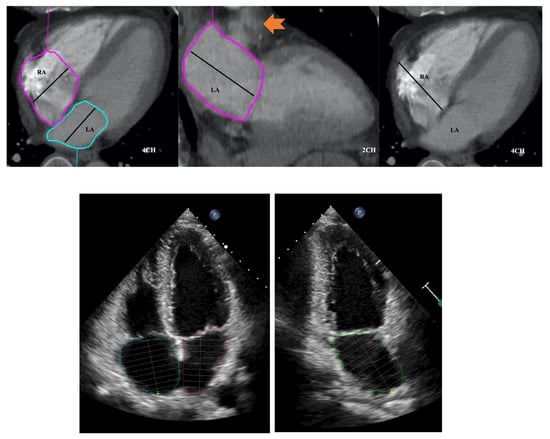

LA area planimetry was performed using freehand ROI tool. Pulmonary veins and LA appendage were excluded. Using TTE area length method, LA volume was estimated by: (0.85 × area 1 (2 chamber) × area 2 (4 chamber)) ÷ shortest LA long axis length []. Whilst limitations of area length method (relating to LA shape geometric assumptions) are acknowledged, it was selected over the Simpson modified biplane method to allow expeditious CT LA volume estimation without the need for additional software computation. Direct LA area was not measured from the straight axial stack due to divergence of LA long axis plane from the standard axial plane which would result in a degree of systematic bias and limit direct comparability with TTE. This would be further compounded by single plane 4 chamber LA measurements being smaller than 2 chamber []. RA volume was also measured from same CT 4 chamber plane without alteration of the horizontal imaging plane to emphasise the RA. Area planimetry was performed using freehand ROI tool with exclusion of RA appendage. Single plane RA volume was estimated by: (0.85 × (RA 4 chamber area)2) ÷ RA long axis length [,]. (Figure 3 and Figure 4).

Figure 3.

Four and two chamber planes from a non-ECG-gated CTPA (top) and corresponding echocardiograpy images (bottom). Atrial areas planimetered with exclusion of right and left atrial appendages and pulmonary veins. Arrow in middle panel indicates left atrial appendage. RA: right atrium; LA: left atrium.